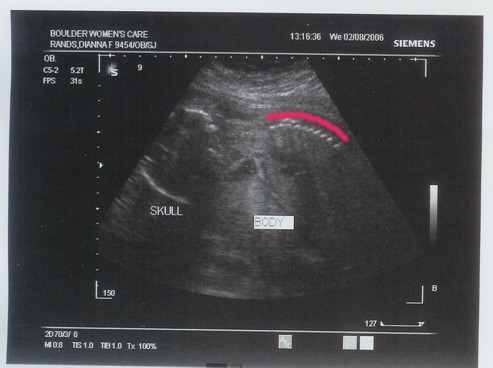

| November 1, 2005 Yesterday was our first doctor's visit and it was purely magical! Since my cycles are irregular, the doctor ordered an ultrasound to determine how far along we are. And of course my calculation was exact! As of yesterday we were 8 weeks and 1 day. While we were having the ultrasound, we also got to listen to the heartbeat! WOW! This little "it" has got one fast ticker. 188 beats per minute. It's high, but the technician didn't seem concerned, so we aren't. So for now, we will call "it" what Grandma Happy called "it": Speedy Gonzales (of course until we know exactly what "it" is ). So without further delay...here is Speedy! There are three photos. One has no alterations, one that outlines the baby, and one that outlines the umbilical cord. |